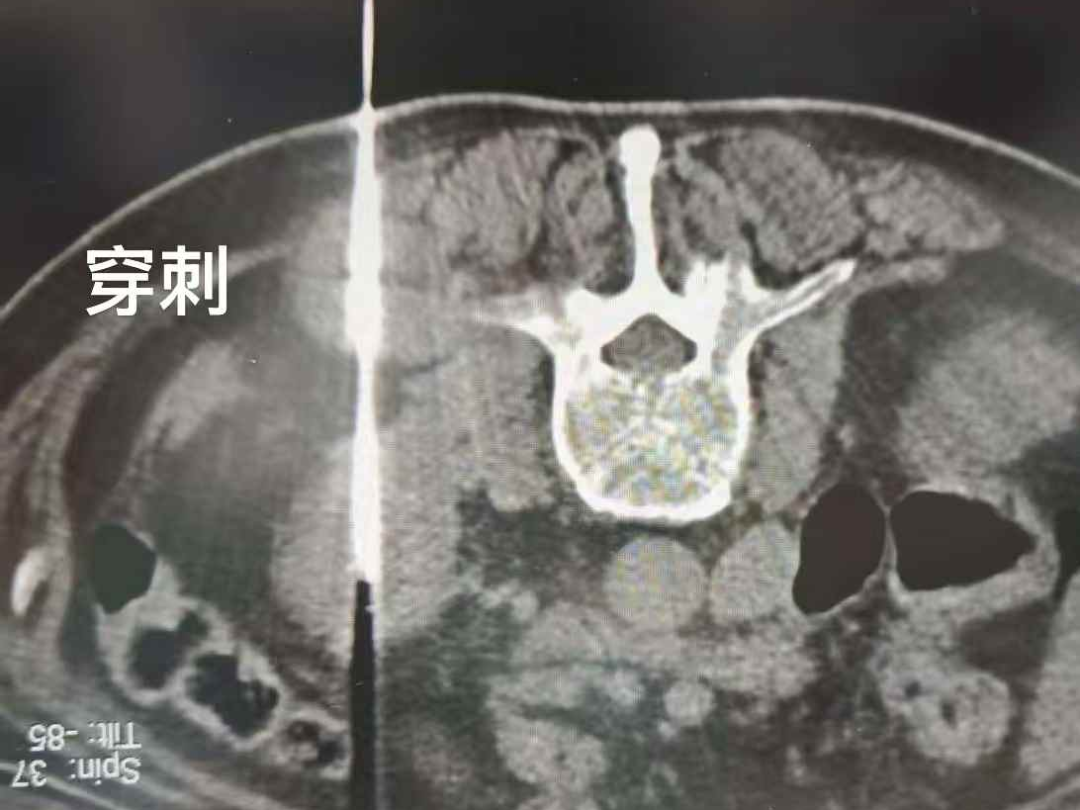

面对肿瘤与血液疾病并存的复杂情况,医疗团队经多学科评估认为,李叔有明确的减瘤治疗指征,但传统手术风险过高。结合家属的强烈意愿与李叔的身体条件,团队最终制定了“冷冻消融术+术后靶向药物治疗”的个体化方案。冷冻消融能以超低温“冻死”肿瘤细胞,创伤小、恢复快,更适合高龄多病的患者。